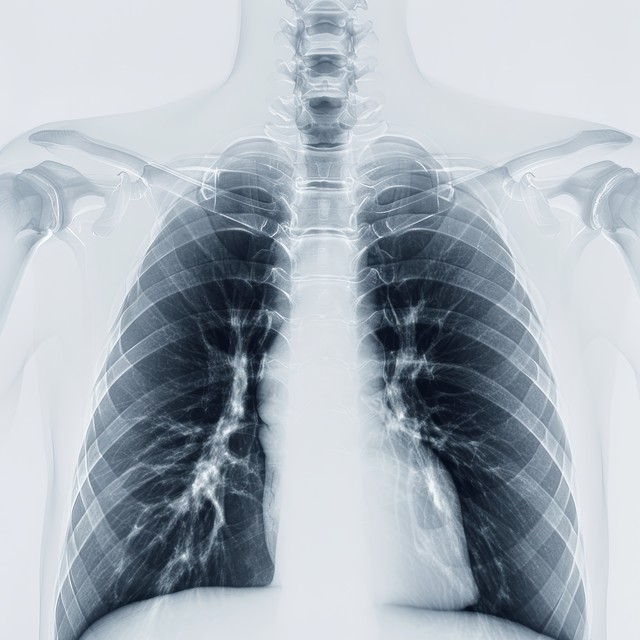

當地醫生说是炎症,她卻坐立不安…自己的直覺,揪出早期肺癌! 一、咳嗽不止查不出原因,醫生说是「炎症」今年48歲的張女士,半年前開始出現輕微乾咳,沒有咳痰、發燒,也沒有胸痛、咯血等症狀。起初她以為是換季受涼,自行吃了些感冒藥,可咳嗽卻時好時壞,持續了兩個多月不見好轉。她去當地醫院做了胸片檢查,報告顯示肺部有少許模糊影,醫生結合症狀判斷為「肺部炎症」,開了抗生素和......【查看全文】